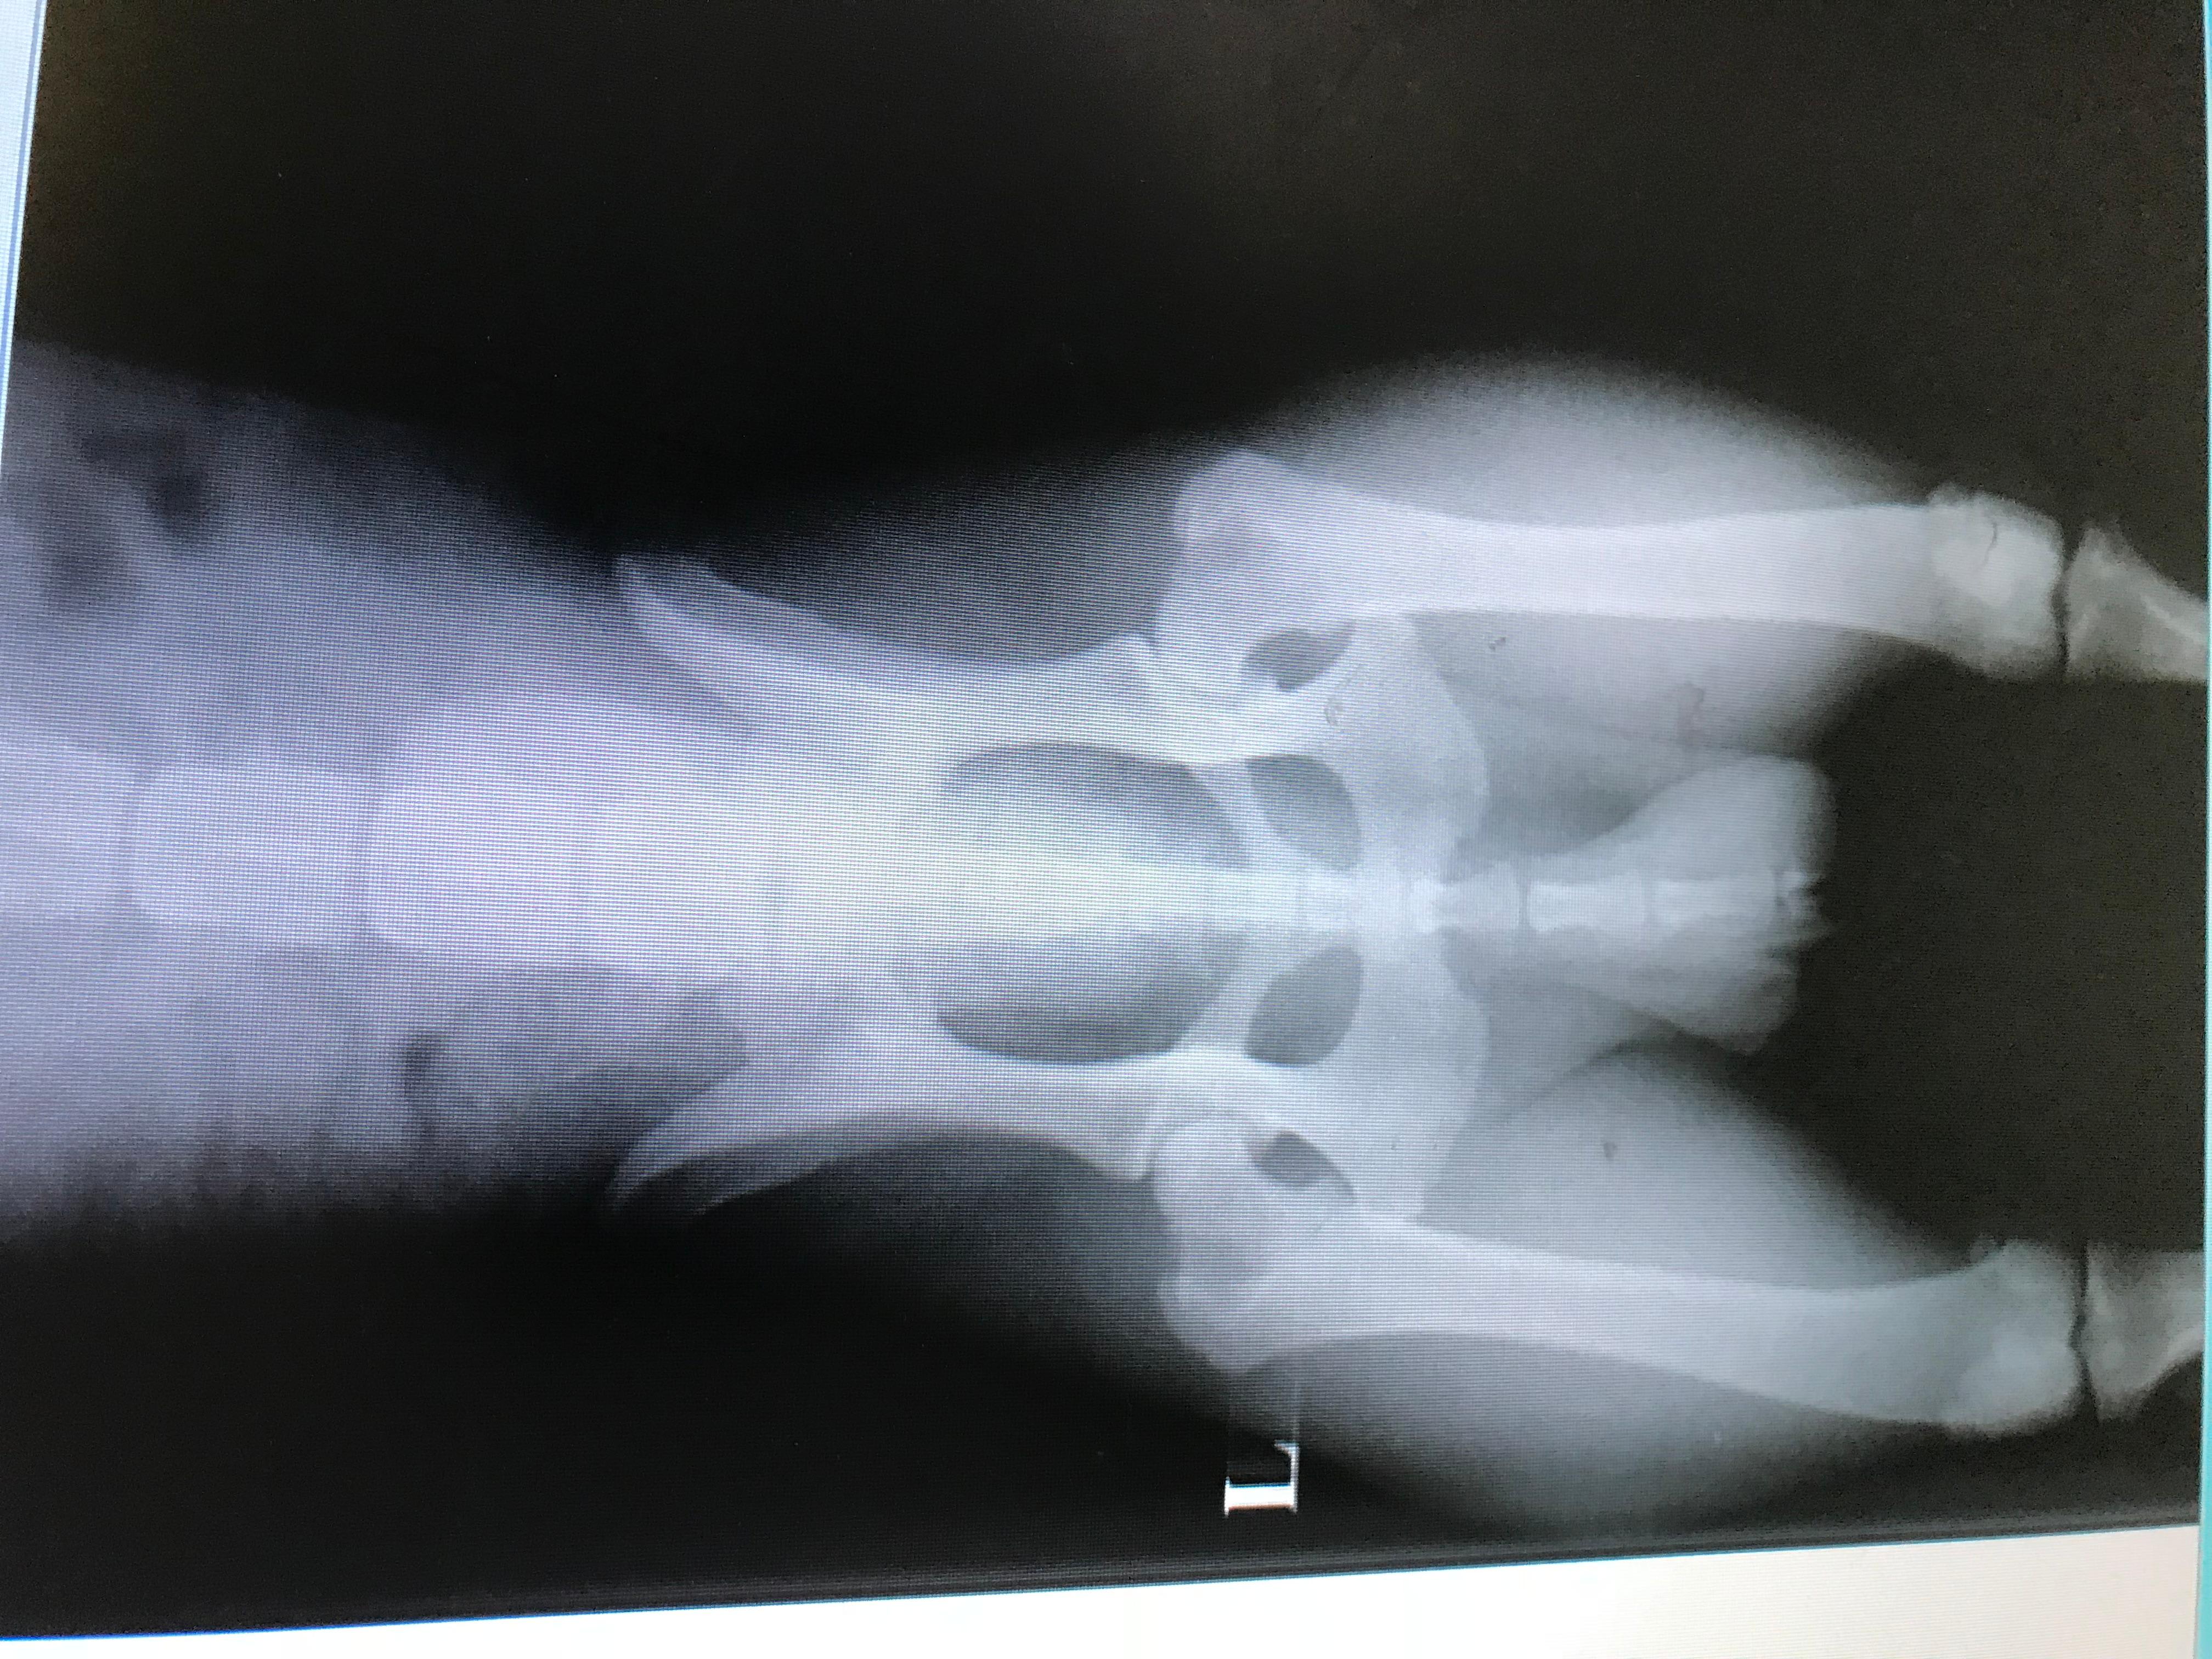

Is my Golden Retriever's hip dysplasia genetic? Can I breed?

Hi My golden retriever have dysplasia and i wonder how can i get it's genetically or traumatic ?he is 3 years and wanna this info for breeding

Unfortunately hip dysplasia is genetic, and it is something that is common in Golden Retrievers. It is never recommended to breed a dog with hip dysplasia due to the genetic component of the disease. In it's most severe form, it can cause crippling lameness and severe arthritis. If you want to breed Toby, you need to get him hip scored by a vet, and only dogs with very low scores should be bred. I hope this helps!